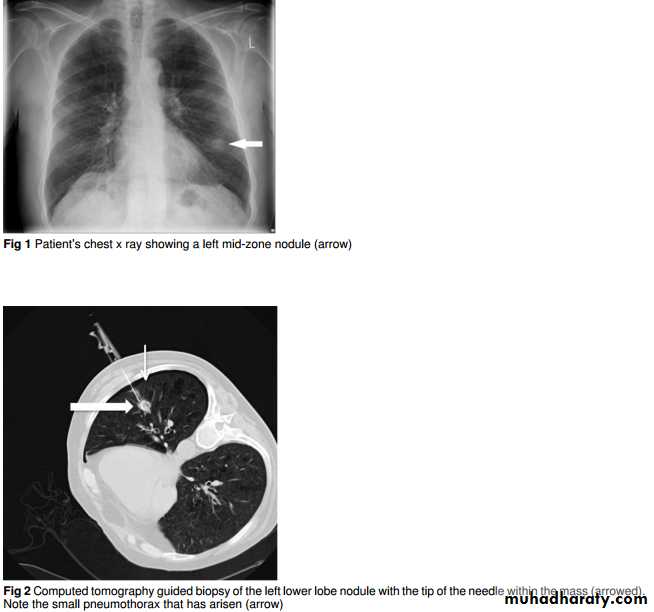

An 81 year old man presented to the emergency department with a one week history of fever, cough, and right sided chest pain. He had had a myocardial infarction in 2004 but was otherwise well. He had a 50 pack-yearsmoking history. Clinical examination was unremarkable. His chest x ray showed a left mid-zone nodule (fig 1⇓). He wastreated for a lower respiratory tract infection and referred to the lung cancer clinic with two week wait for an appointment.

Computed tomography revealed a 17 mm peripheral nodule staged as T1aN0M0. The patient was counselled regarding treatment options and was initially keen to know a diagnosisand consider surgery. The nodule was biopsied percutaneously under computed tomographic guidance, complicated by a small pneumothorax that did not require intervention (fig 2⇓).